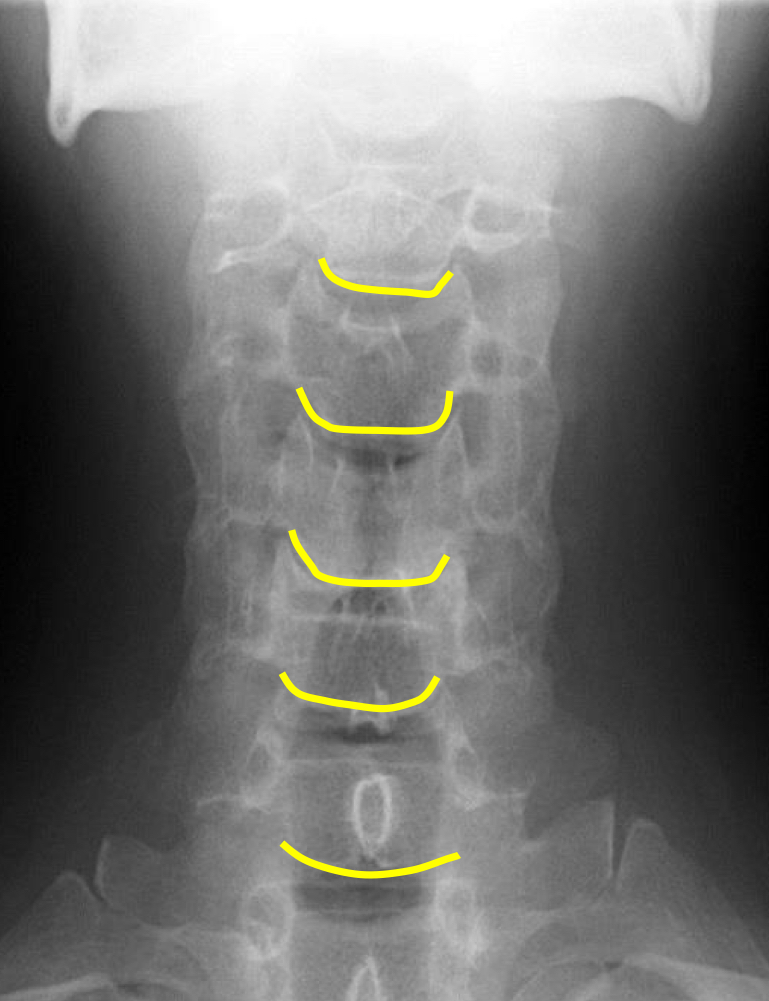

What view is this?

AP (Anterior to Posterior) Cervical

What is this?

Junction of Lamina/tip of Spinous

What is this?

Uncinate Processes

What is this?

Inferior Aspect of Vertebral Bodies